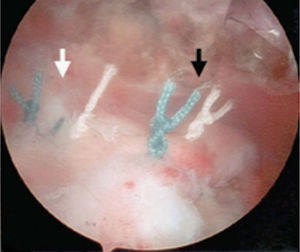

En la técnica de doble fila se colocan uno o dos anclajes mediales en el borde articular de la cabeza humeral, se pasan puntos sencillos a través del tendón y se anudan las dos suturas de cada anclaje con nudos deslizantes bloqueados. Los anclajes laterales se colocan en el borde lateral de la tuberosidad mayor y se anudan con las suturas mediales, ya sea con nudos deslizantes bloqueados o con los sistemas de no nudos existentes en el mercado. Una de las principales complicaciones en la reparación del manguito de los rotadores es la rerrotura, pero es muy importante tener en cuenta que en muchas ocasiones no existe una correlación directa entre una rerrotura, ya sea parcial o completa, con los resultados clínicos y funcionales44. Sin embargo, existe una relación directa entre la cicatrización y la fuerza postoperatoria (figs. 17–19).